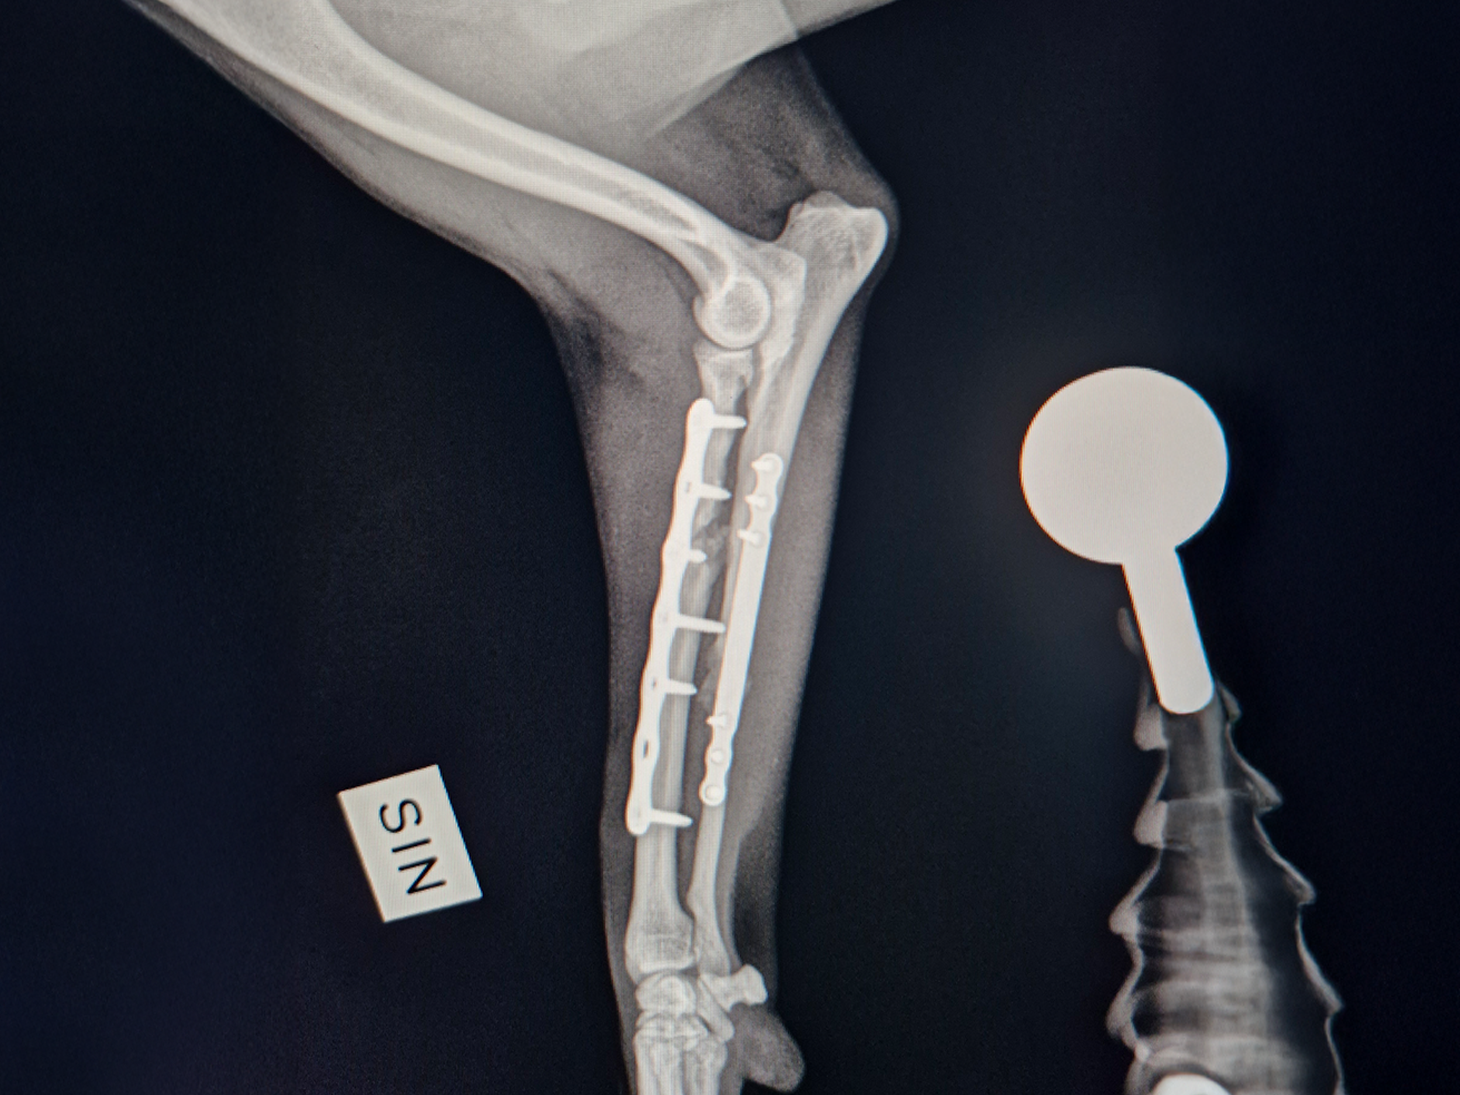

Case Overview

In April 2025, a 3-year-old, 5.6 kg mixed breed dog suffered a severe injury after being struck by a bicycle. The patient presented with a complex proximal comminuted radius fracture and a mid-diaphysis ulnar fracture, classified as an open fracture Grade 1. Thanks to swift surgical intervention and advanced technology, the dog is now back to its energetic self.

The complex, dual-bone injury required a sophisticated approach performed by Dr. Ditte Skytte.

- The severely comminuted radius fracture was stabilized using a 2.0 mm titanium LeiLOX plate, specifically chosen to manage the comminution in combination with a supportive repair of the ulna.

- The ulna fracture was addressed with our innovative 1.0 mm titanium LeiLOX plate, secured by 1.3 mm locking screws. This combination provided robust, yet minimally disruptive, fixation crucial for a small patient. The surgical site was thoroughly flushed, and the patient received Cefazolin both perioperatively and for three days post-op to manage the open wound.

- X-Ray Confirmation: The surgery sites were fully healed, with no discomfort upon palpation. X-rays showed advanced healing with significant callus formation and all implants intact.